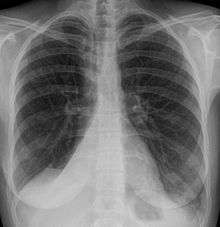

Atelectasis of a person's right lung | |

Atelectasis is the collapse or closure of a lung resulting in reduced or absent gas exchange. It may affect part or all of a lung.[1] It is usually not bilateral. It is a condition where the alveoli are deflated down to little or no volume, as distinct from pulmonary consolidation, in which they are filled with liquid. It is often called a collapsed lung, although that term may also refer to pneumothorax.[2]

It is a very common finding in chest x-rays and other radiological studies. It may be caused by normal exhalation or by several medical conditions. Although frequently described as a collapse of lung tissue, atelectasis is not synonymous with a pneumothorax, which is a more specific condition that features atelectasis. Acute atelectasis may occur as a post-operative complication or as a result of surfactant deficiency. In premature neonates, this leads to infant respiratory distress syndrome.